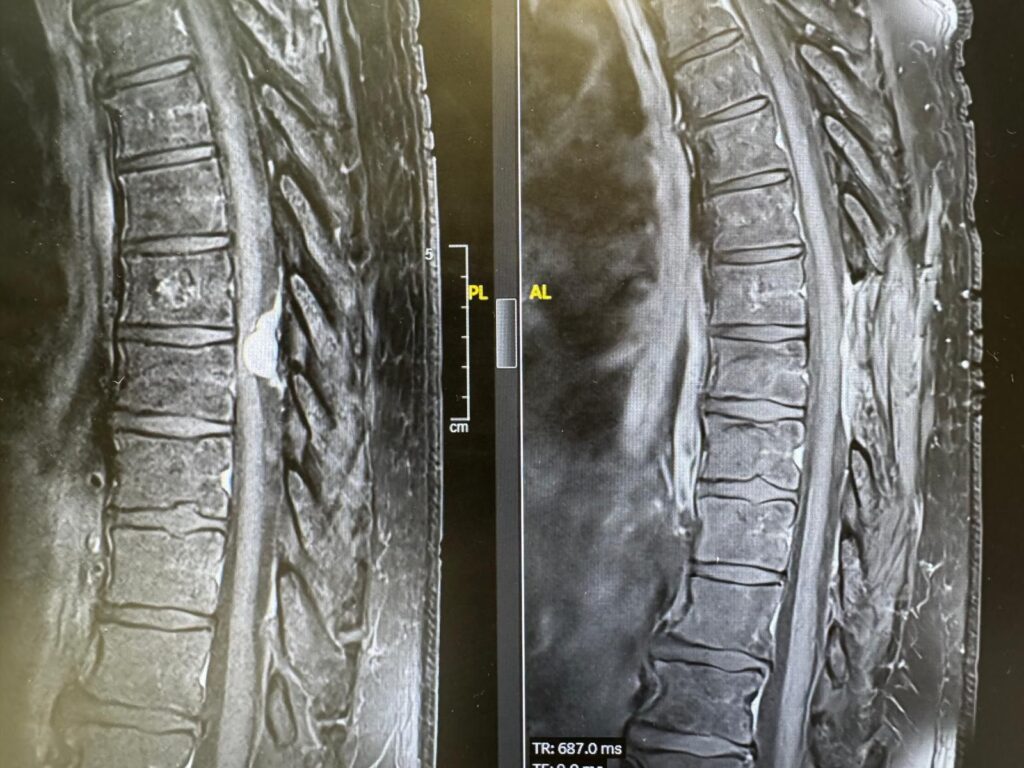

מניגיומה של עמוד השדרה הוא גידול שפיר שנמצא בתוך הקרומים של עמוד השדרה. הגידול, שנפוץ בעיקר בקרב נשים בגילים מבוגרים יותר, גורם ללחץ על עמוד השדרה ועל העצבים ומוביל לתסמינים שונים בידיים וברגליים, ובהם, נימול, חולשה בגפיים, בעיות בהליכה ואף לשיתוק.

רק כשהגעתי לשערי צדק הבינו, לאחר שד"ר מרדכי לין מהמחלקה הניורולוגית עשה לי בדיקת MRI, שיש לי גידול שפיר בעמוד השדרה בגודל של כדור טניס. הגידול הוסר בניתוח ומיד לאחריו התחלתי להרגיש שיפור והצלחתי להזיז את רגל שמאל. בזכות הצוות המדהים של הרופאים והאחיות בשערי צדק, אני מצליחה לעשות היום משהו שלא יכולתי בעבר. מעולם לא קיבלתי יחס כזה מצוות רפואי – הם פשוט מלאכים, אין לי מילה אחרת, לא רציתי לעזוב את בית החולים מרוב שהחוויה הייתה טובה".

ד"ר גוסטבו רייז, ניורוכירורג בכיר במרכז הרפואי שערי צדק, שביצע את ארבעת הניתוחים, סיפר: "לאורך השנים, לא נתקלתי מעולם בכמות מקרים גבוהה כל כך של נשים שאובחנו עם מניגיומה בעמוד השדרה ונזקקו לניתוח בפרק זמן כה קצר בעקבות כך. התרגשתי לראות נשים מבוגרות, שאיכות חייהן נפגעה מאוד, כאשר חלקן סבלו משיתוק כמעט מלא של אחת מהרגליים, ובעקבות הניתוח מצבן השתפר והן הצליחו להזיז את הרגליים שוב. חשוב להדגיש שמדובר בגידול שניתן לטפל בו ולכן קיימת חשיבות רבה לגילוי מוקדם ככל שניתן. במידה שמופיעות תופעות ניורולוגיות כלשהן, גם אם יש ספק, אני ממליץ להתייעץ עם רופא מומחה ולבצע בדיקות דימות בהתאם".